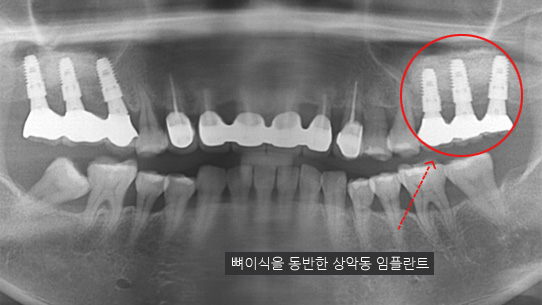

심한 염증과 기존 보철물의 오염상태가 심해 다른 병원에서 임플란트 17개 진단을 받고 내원, 특히 앞니부분의 치조골이 많이 약해져 흔들림이 심하여 바로 치주치료를 시행하였습니다. 치주치료 2주 후 앞니 잇몸이 개선되어 발치 하지 않고 교정 유지장치를 이용하여 흔들림을 보완하였습니다. 오염된 보철물을 제거하고 임플란트 11개를 식립하였습니다.

또한 발치를 하더라도 잇몸 속 뼈의 건강이 회복 되기 때문에

견고한 임플란트 수술이 가능합니다.